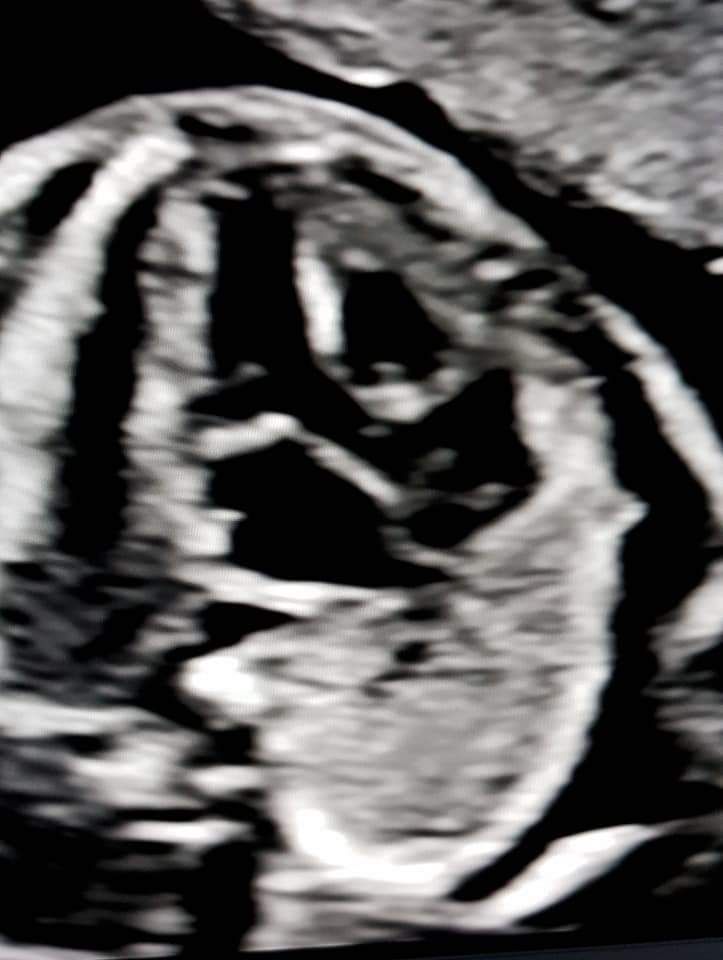

Foto e video

• Studio Ginecologico- Dott.ssa Nadia Fichera ecocardiografia fetale  •